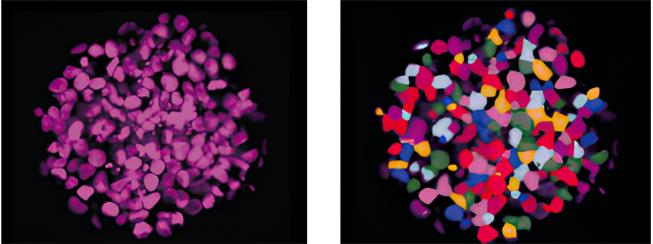

Left: Original image. Right: Recognition image. Image Credit: Yokogawa Life Science

Yokogawa’s spinning disk confocal technology excels in imaging deep samples, such as 3D culture samples, where clear and rapid imaging is difficult. This allows for evaluations that are similar to in-vivo quality.